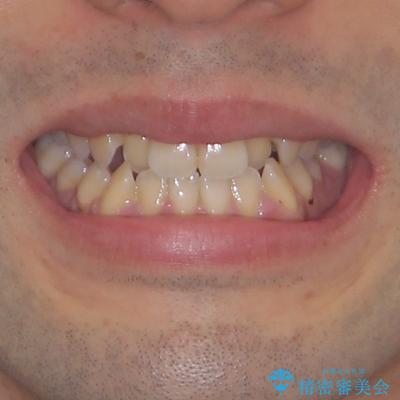

- 前歯のデコボコを気にして来院された患者様です。

歯列としてはワイヤー装置でもインビザラインでも対応可能でしたが、インビザラインが苦手とする上顎側切歯(真ん中から2番目の歯)の舌側転位が顕著でした。

治療の確実性を上げるために、インビザライン開始前に上顎のワイヤー装置にて舌側転位を解消し、その後インビザラインにて矯正治療を行うこととしました。

前歯のデコボコが早めに改善され、スムーズに治療を終えることができました。